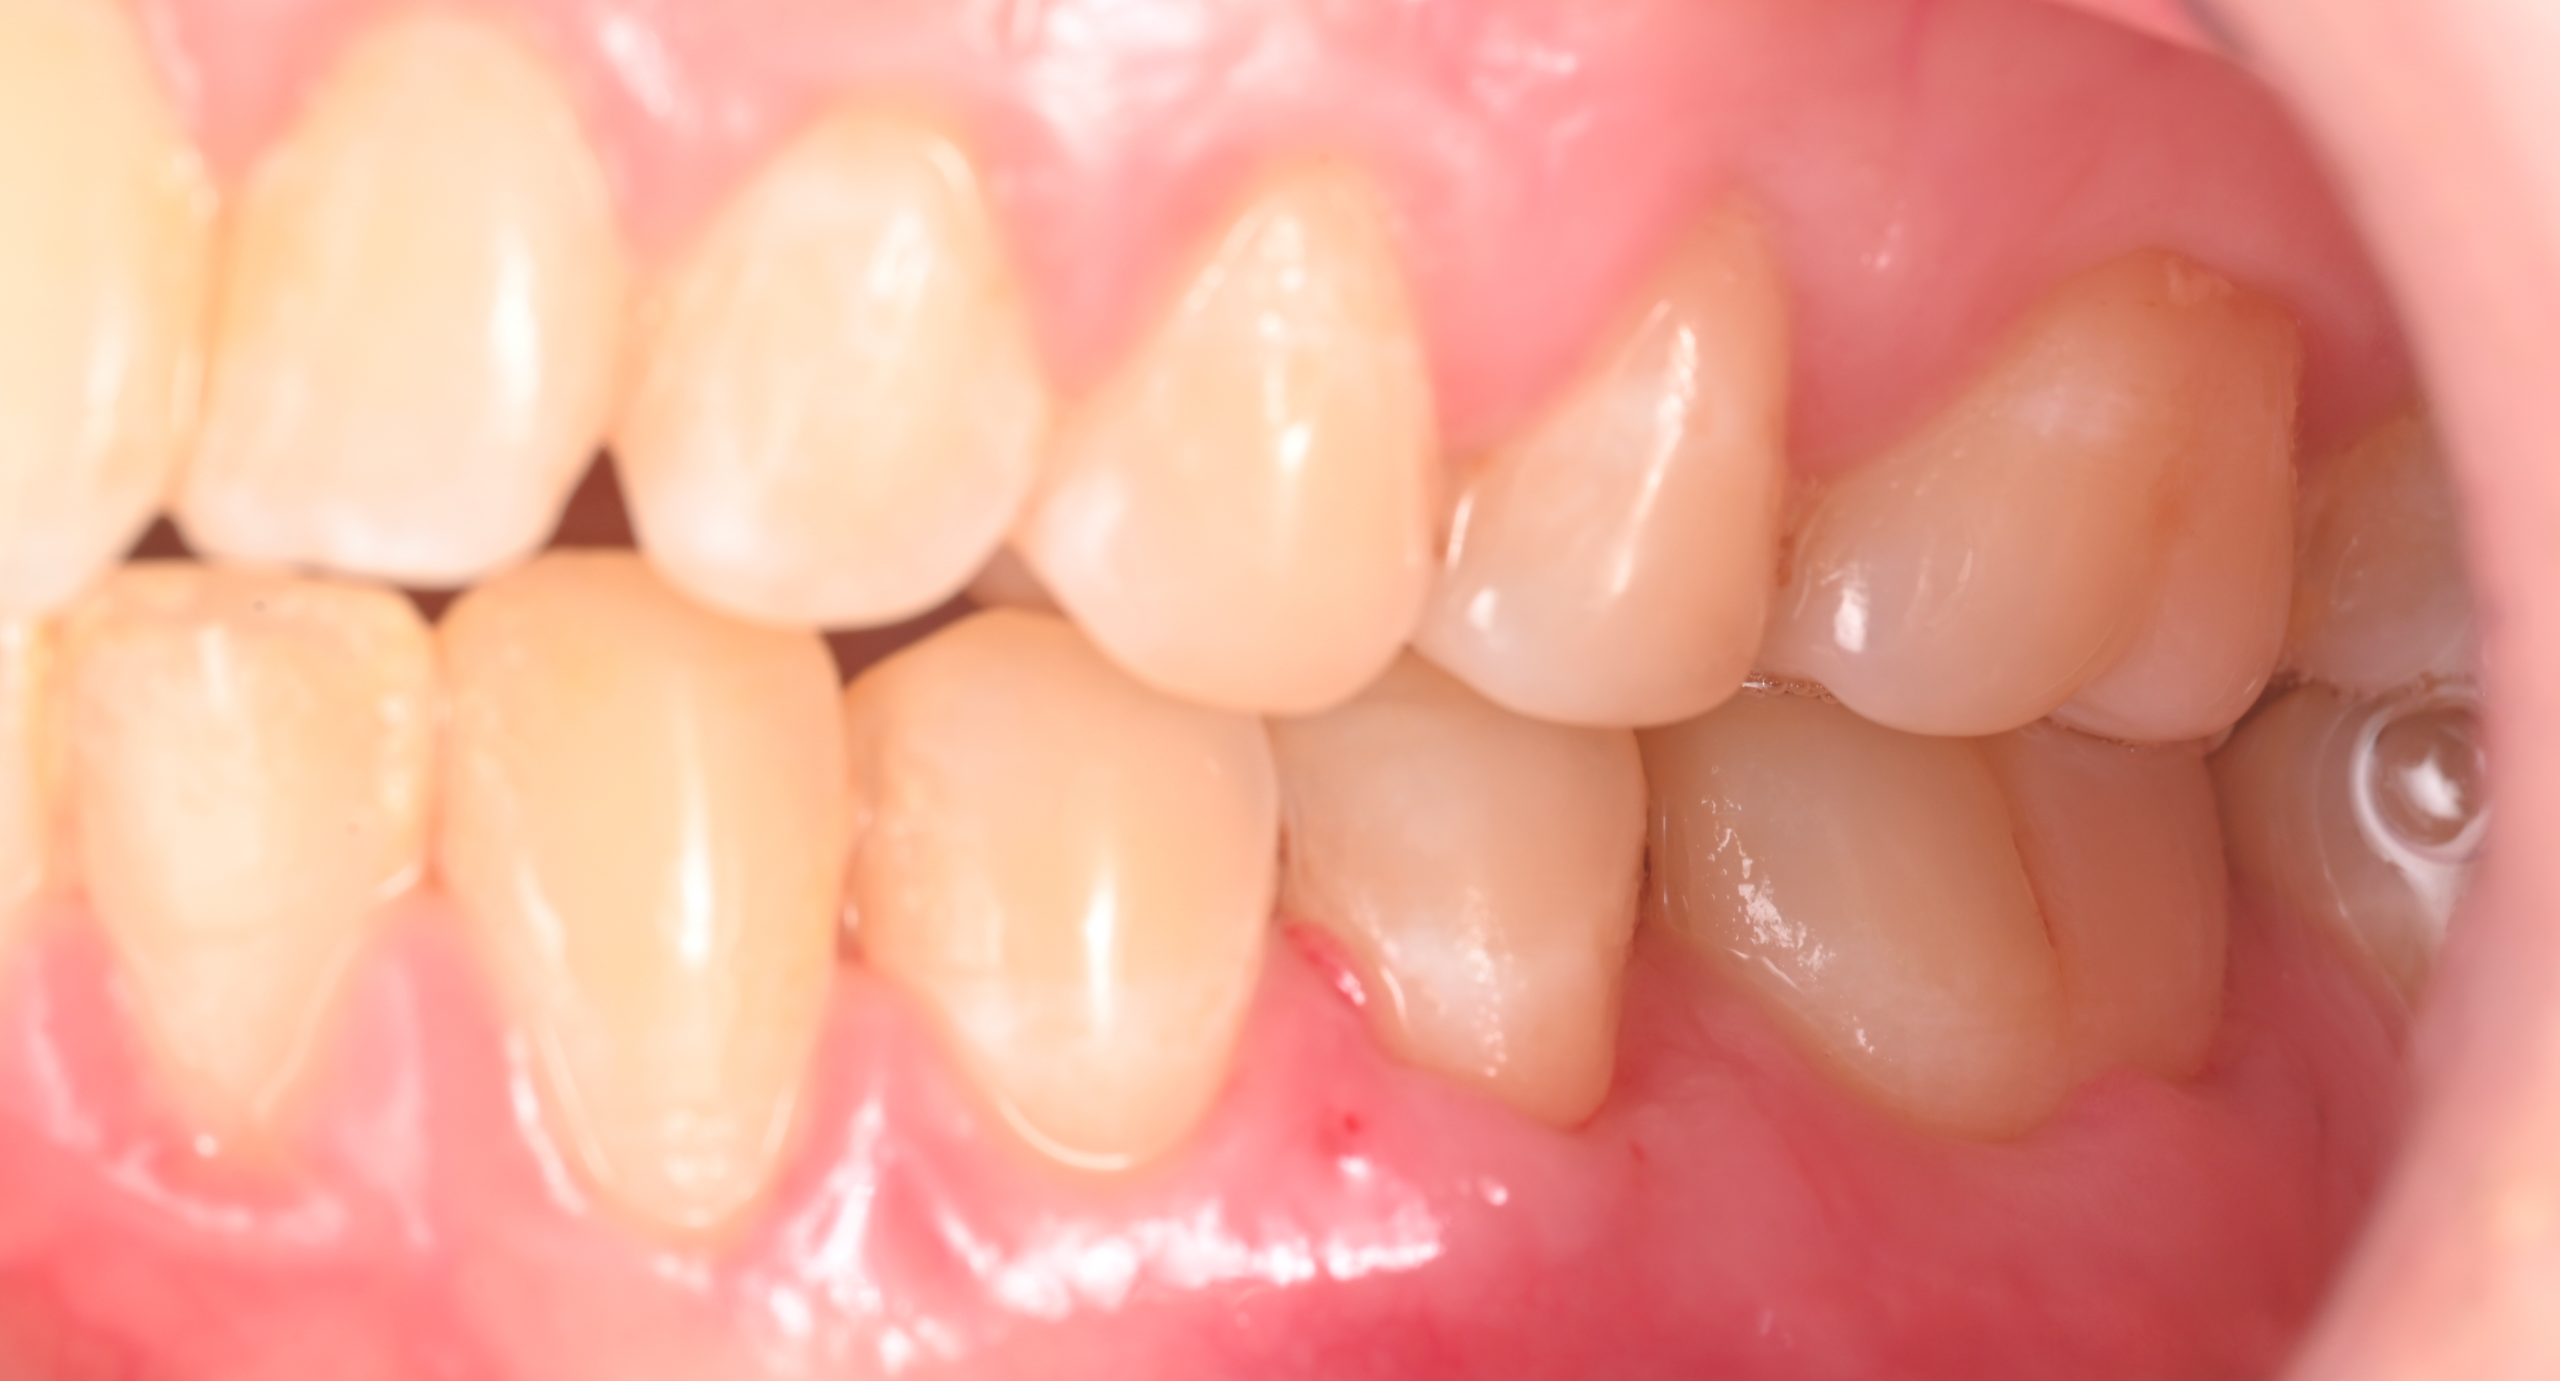

La récession gingivale correspond à un retrait progressif de la gencive qui expose la racine de la dent. Cela peut provoquer :

Une gêne esthétique (dents plus longues).

Un risque de caries radiculaires ou de perte d’attache.